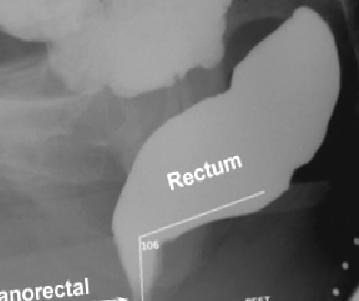

REKTOSEL Şekil normal DEFEKOGRAFİ resmidir. Dışkılama sırasında, ıkınma ve istirahat sıralarındaki, barsak açılanmaları, barsağın dolu ve boşalmış hali, boşalma sırasında barsağın bir tarafına doğru balonlama yapıp yapmaması teşhis için değerli bilgiler sağlar. Defekografi eski yöntem düşüncesi ile hekimler tarafından istenmemektedir. Ancak bu tetkikin yerini tutacak başka bir yöntem yoktur.